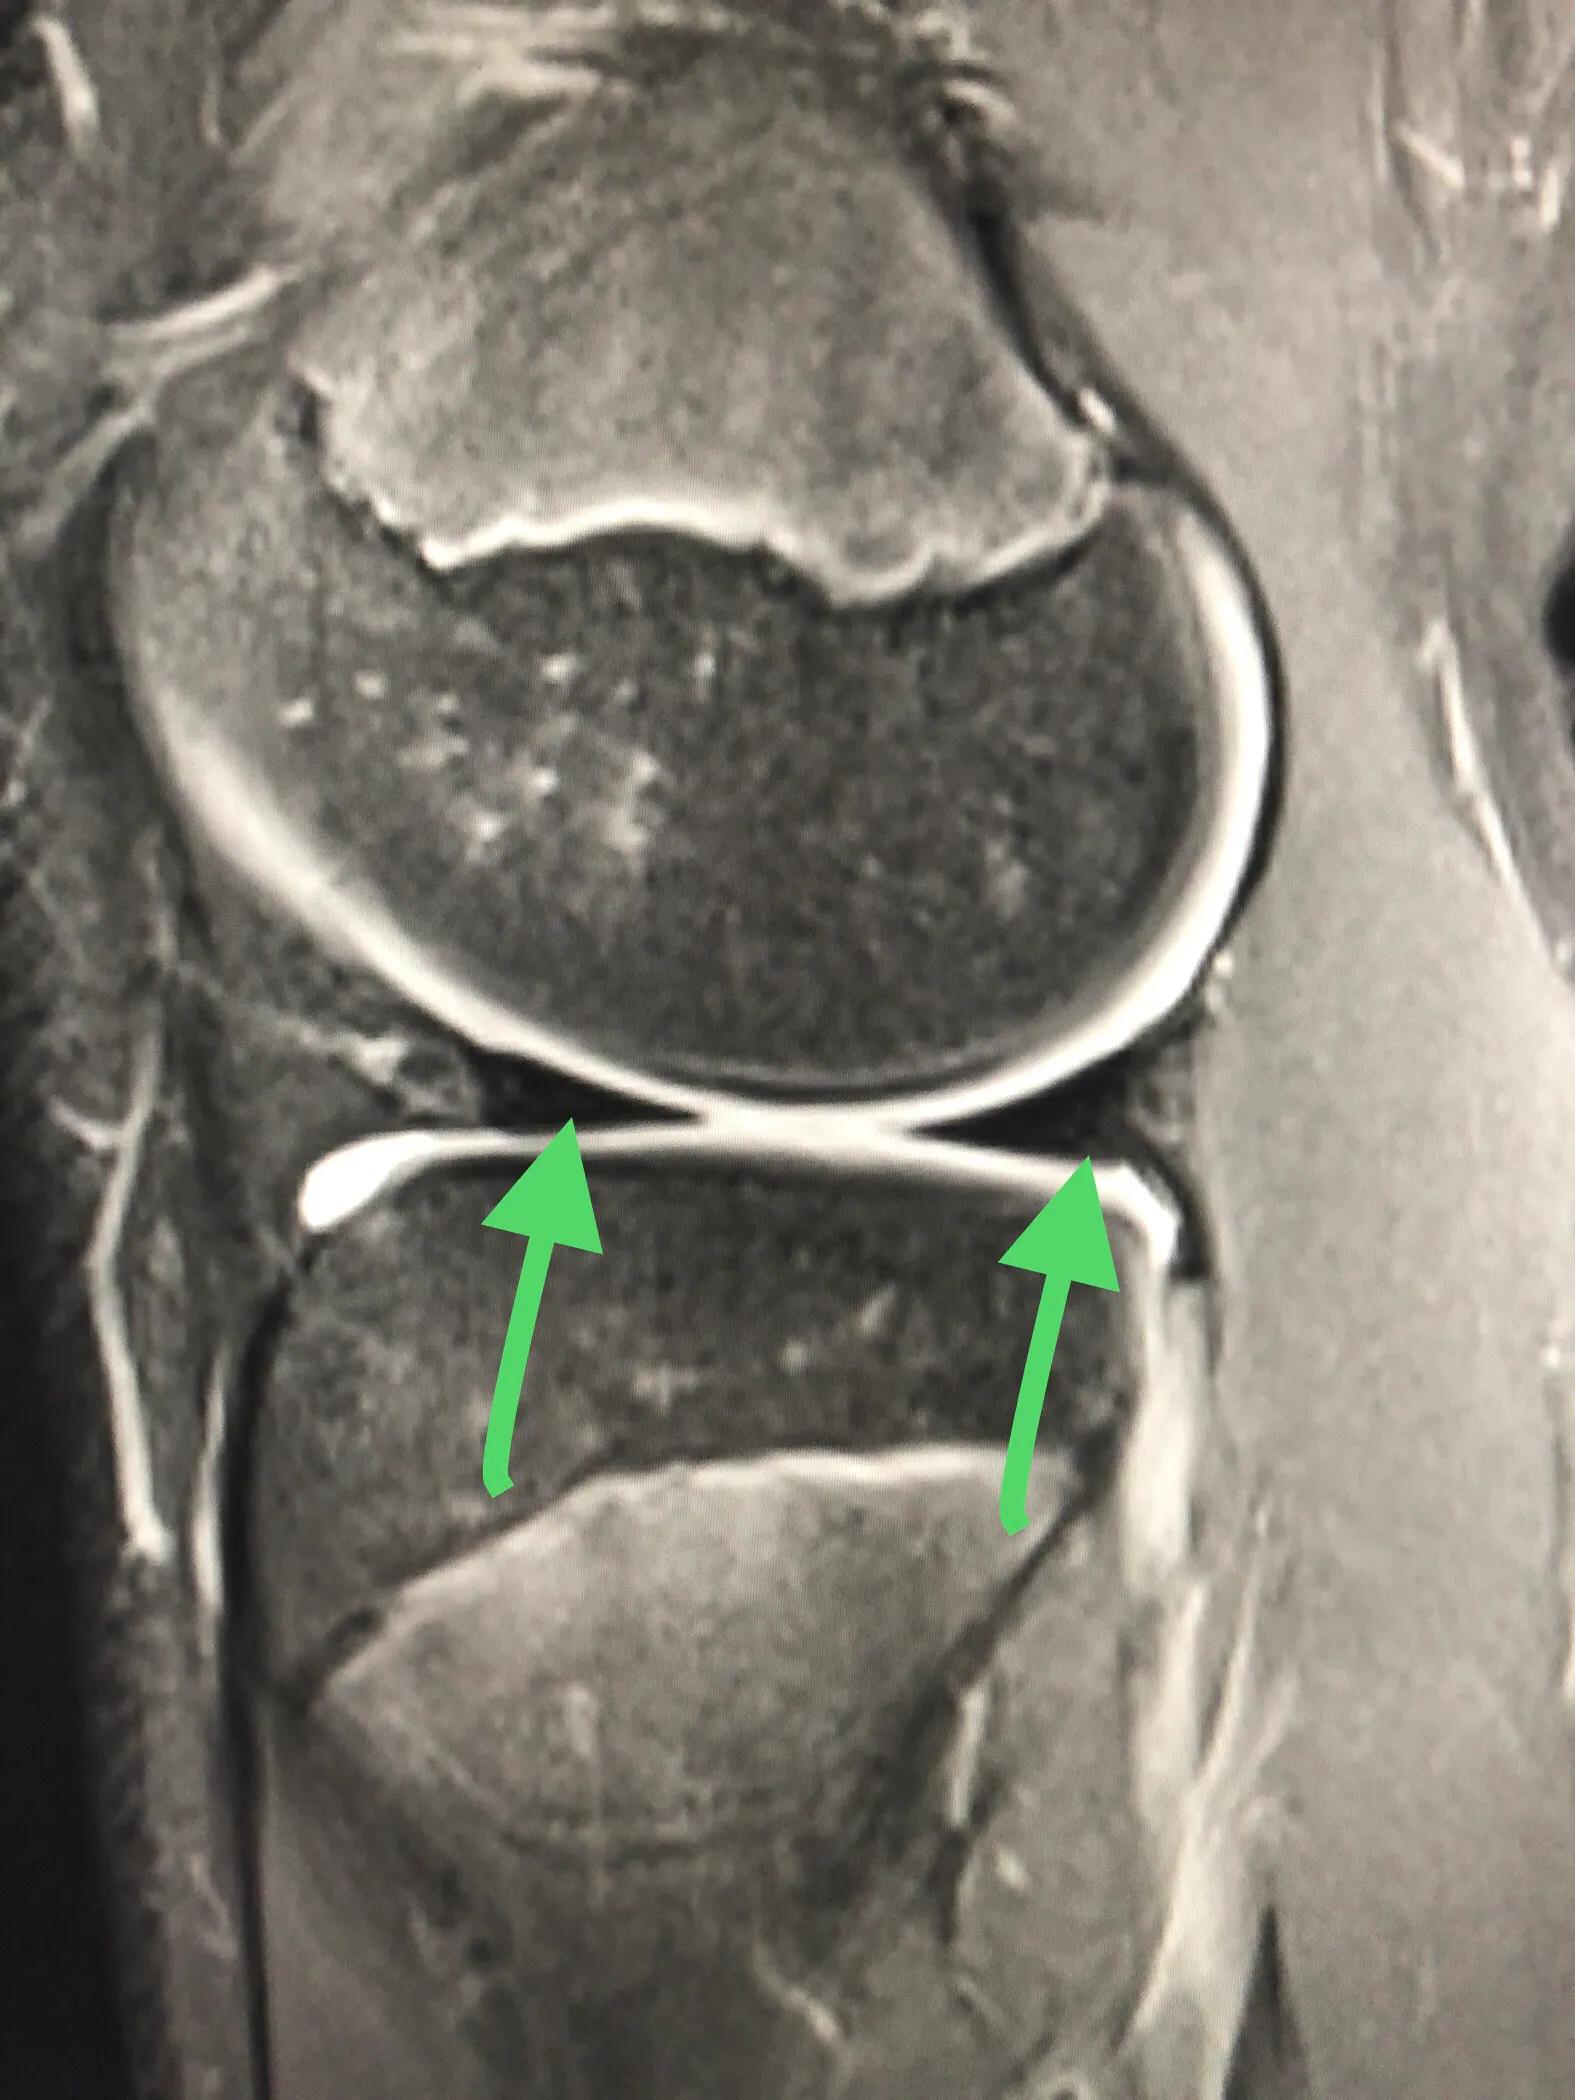

外侧盘状半月板的桶柄样撕裂:两枚绿箭头之间的条状物便是盘状半月板,已经撕裂,需要手术。

换个方向看肥厚的盘状半月板,绿箭头之间的那块便是,已经撕裂,需要手术。